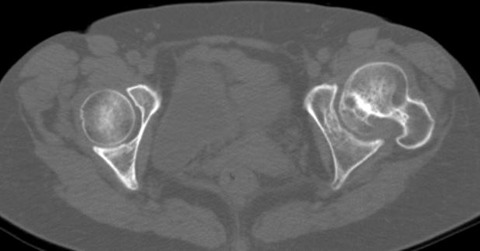

しかし、術前CTで寛骨臼の前方開角が45度、大腿骨頚部前捻角が40度でした...。大腿骨頚部前捻角はまだしも、寛骨臼前方開角は看過できません。

このままの角度でカップを設置すると前方脱臼する可能性があります。しかし、前方開角を減じるとカップ前方で腸腰筋との Irritationを併発して股関節痛を残す原因となりそうです。